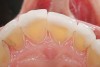

Figure 1  Classic presentation of the bruxism triad. Lateral wear pattern, generalized buccal tooth loss from erosion and abrasion, and history of sleep disruption.

Figure 1